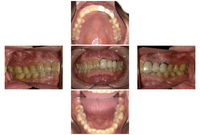

術前